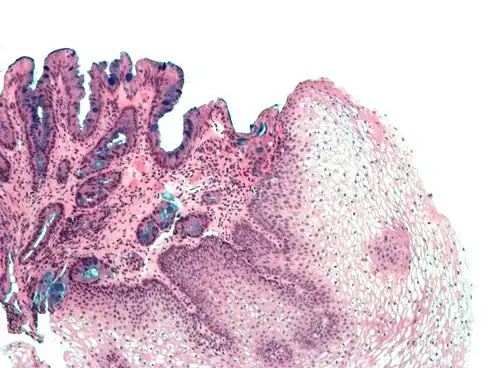

| Tinciones para carbohidratos | ||||

| Tinción PAS | Tiñe carbohidratos y proteínas glicosiladas de color rojo magenta. |

| ||

| Tinción con Lugol | Tiñe el almidón de azul, el glucógeno de amarillo y el resto en tonos de ocre. | |||

| Tinción con carmín | Tiñe el glicógeno de intenso color rojo. |